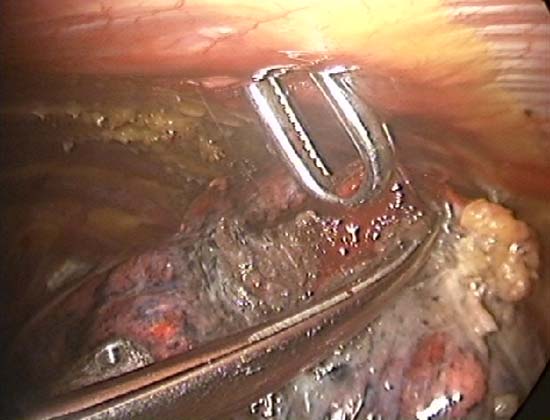

Slightly longer time is needed for resection using the TissueLink device. It is excellent in sealing small (1mm or less) bronchioles in the resection bed. The floating ball device should be applied directly over the bronchiole for one to two minutes to accomplish this. The TissueLink device, by nature of the technology, generates less smoke than conventional electrocautery. However, a small amount of steam is inevitable, and it is advisable to keep a sucker (a conventional Yankauer sucker works best) close to the surgical field, which also may be used to exert counter-traction on the lung tissue to facilitate dissection (Figure 5). As with all potential cancers, specimens should be placed in a bag before they are removed through a port site (Figure 6).